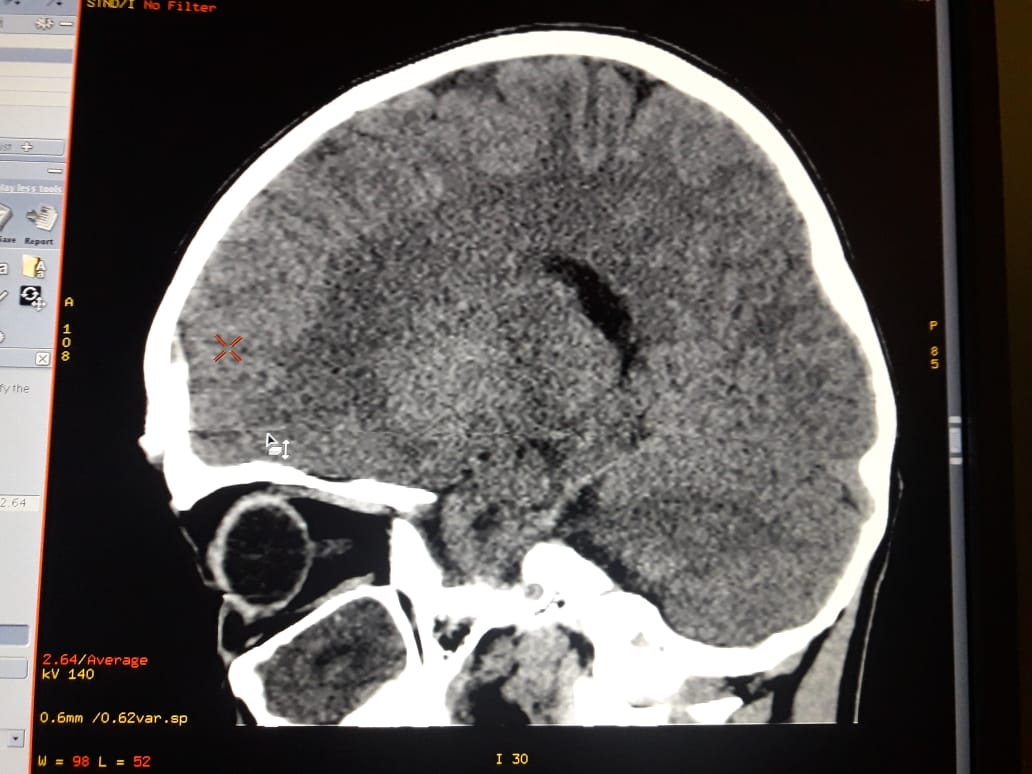

В Жанаозене ребенок упал с высоты четырех метров и выжил

Благодаря усилиям врачей, упавшего семилетнего мальчика спасли. Сейчас состояние ребенка стабильно тяжелое. Об этом сообщили в управлении здравоохранения Мангистауской области.

Инцидент произошел в ночь с 27 на 28 февраля в Жанаозене. По словам родителей, их сын, играя на стройке, упал с высоты четырех метров и ударился об камень.

- Пациент - мальчик 2012 года, с диагнозом тяжелая открытая черепно-мозговая травма, вдавленный перелом лобной кости, кортикальный ушиб левой лобной доли. Ушибленная рана лобной области. Из областной детской больницы в Жанаозен в экстренном порядке выехал детский нейрохирург Ербол Кенжевалов. Произведена первичная хирургическая обработка раны, наложены швы, - сообщили в управлении здравоохранения Мангистауской области.

По словам врача, могут быть вторичные осложнения, такие, как нагноения послеоперационной раны, менингит или вентрикулит - из-за сильного загрязнения раны, от песка и грязи.